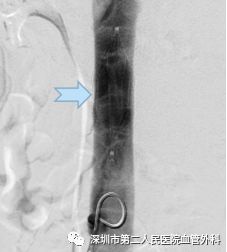

CDT是将带有很多侧孔的溶栓导管,通过静脉穿刺的方法插入血栓中,将溶栓药物通过侧孔持续推注到血栓中,可获得很好的溶栓效果(图10-12)。这种方法对静脉壁损伤轻微,而且能较好地保护静脉瓣的功能。

图11 左:髂静脉内的血栓(白色)。右:置管溶栓后髂静脉恢复通畅

通过适当的手术治疗,肿胀能有效缓解,而且预后较保守治疗好,一般不会出现严重的血栓后综合征。当然,手术后也需要坚持抗凝治疗和弹力袜压力辅助治疗。

图12 微创CDT手术溶栓治疗前(左)、后(右)